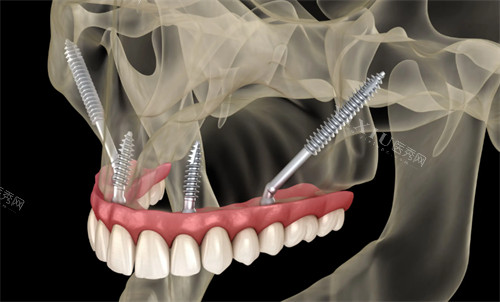

穿颧种植技术是一种新型的口腔种植解决方案,适用于上颌骨严峻萎缩、牙槽骨骨量不足的患者。该技术通过将种植体植入颧骨或翼骨,利用这些部位的坚固骨质来提供稳定的支撑,从而避免了传统种植手术中复杂的骨增量过程。与传统种植技术相比,穿颧种植具有手术时间短、创伤小、改善快等优点。

无骨量限制:即使牙槽骨完全吸收,也能通过颧骨或翼骨的支撑完成种植。

即刻负重:患者在种植手术后可以立即安装临时牙冠,术后当天即可改善咀嚼功能。